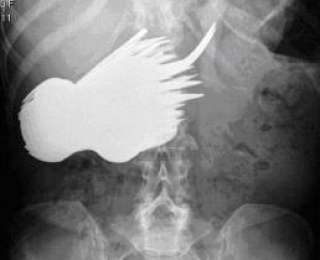

Как вы думаете, что изображено на этом снимке? Честно вам скажу, отгадать с первого раза будет очень непросто.

Хоть в это и верится с трудом, но это рентгеновский снимок желудка женщины, которая проглотила!! 78 вилок и ножей.